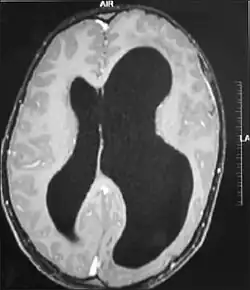

MRI images showing megalencephaly in four family members who all have unusually large skulls (the family is affected by an autosomal recessive syndrome caused by a KIF7 mutation that induces multiple epiphyseal dysplasia)[1]